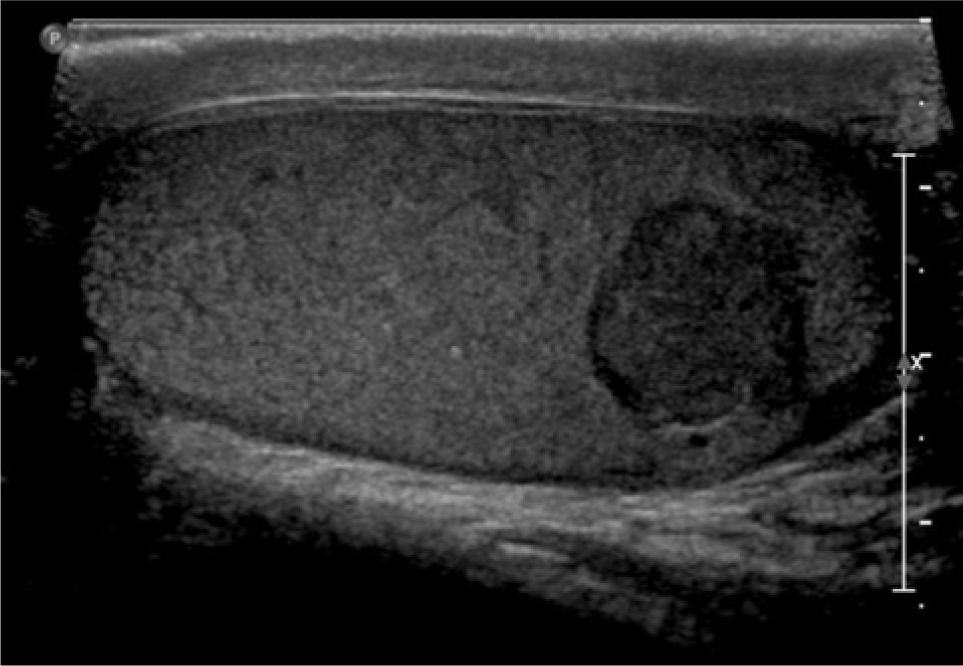

Core biopsy confirmed metastatic clear cell RCC in the paraspinal mass. The mediastinal and bilateral parenchymal masses were resected. Pathology for the mediastinal and left lung masses was positive for clear cell RCC, while hamartoma was confirmed in the right lobe. A PET/CT done 1 year later, showed suspicious uptake in the adrenal lesions being monitored. The right mass had a standardized uptake value (SUV) of 2.7, while the left mass had an SUV of 2.9. Labs showed normal levels of aldosterone, cortisol, plasma metanephrines, and normetanephrines. Biopsy of the right adrenal mass revealed pathology consistent with metastatic RCC. After an initial period of surveillance, the patient chose to proceed with systemic therapy and enrolled on a clinical trial. He had stable disease for 2 years when a CT urogram revealed a 1.7-cm enhancing right lower pole testicular mass (Figure 1). Physical examination revealed a palpable right lower pole testicular mass. Testicular cancer serum tumor markers were within normal limits. Ultrasound showed a 1.5 cm hypoechoic, hypervascular right lower pole mass (Figure 2). CT scans showed stability of prior metastatic lesions.

Figure 2: Ultrasound image showing 1.4 × 1.5 × 1.5 cm hypoechoic mass in the lower pole of right testicle.